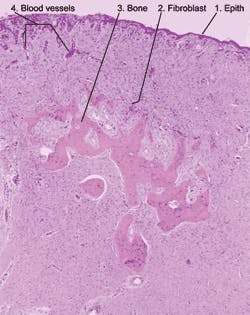

Significant microscopic features: Microscopically, the tissue is composed primarily of cellular fibroblasts with various types of calcification including bone, cementum and dystrophic calcification. The surface epithelium may exhibit varying degrees of ulceration (see Figure 2).

In the slide, the following areas are identified:

- Surface epithelium

- All small blue dot-like cells are nuclei of the lesion’s cells, fibroblasts

- Bone

- Dilated blood vessels due to the inflammation within the lesion